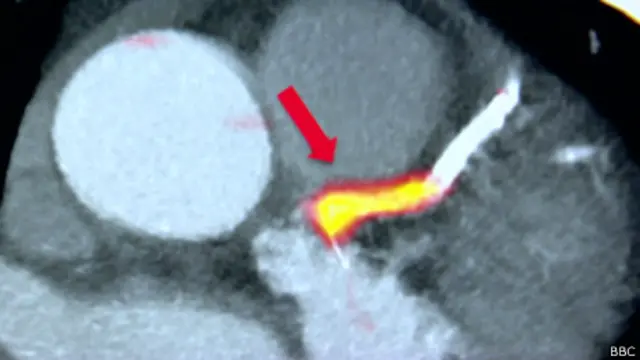

A técnica detecta a formação de placas nas artérias que levam sangue ao coração. Se uma dessas placas de gordura se rompe, a artéria pode ficar obstruída, bloqueando o fluxo do sangue e provocando o ataque cardíaco.

Eles usaram um marcador radiativo – uma substância química que ajuda a detectar as placas. Os cientistas conseguem visualizar essas placas com imagens de alta resolução do coração e das veias sanguíneas.

Assim, eles conseguem obter um retrato detalhado do coração, com as zonas de perigo claramente identificadas. Uma técnica semelhante é usada para detectar o local exato de tumores em pacientes com câncer.